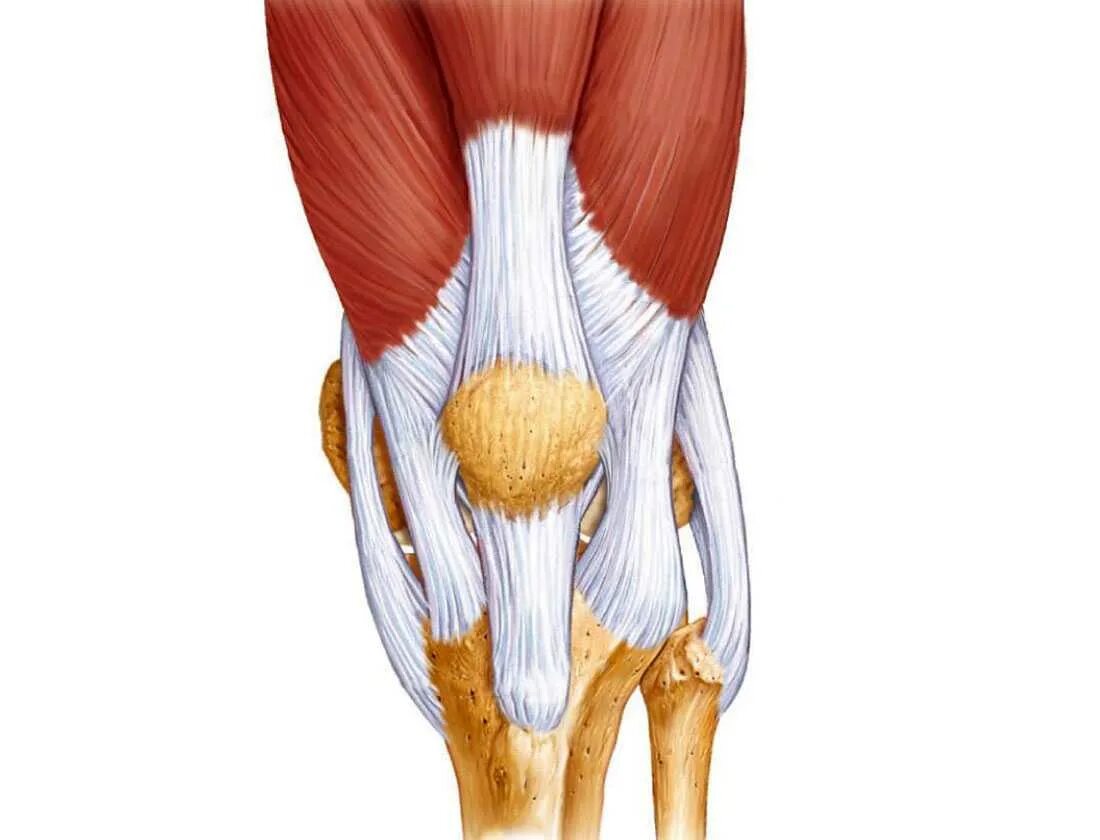

Воспаления сухожилий тазобедренного